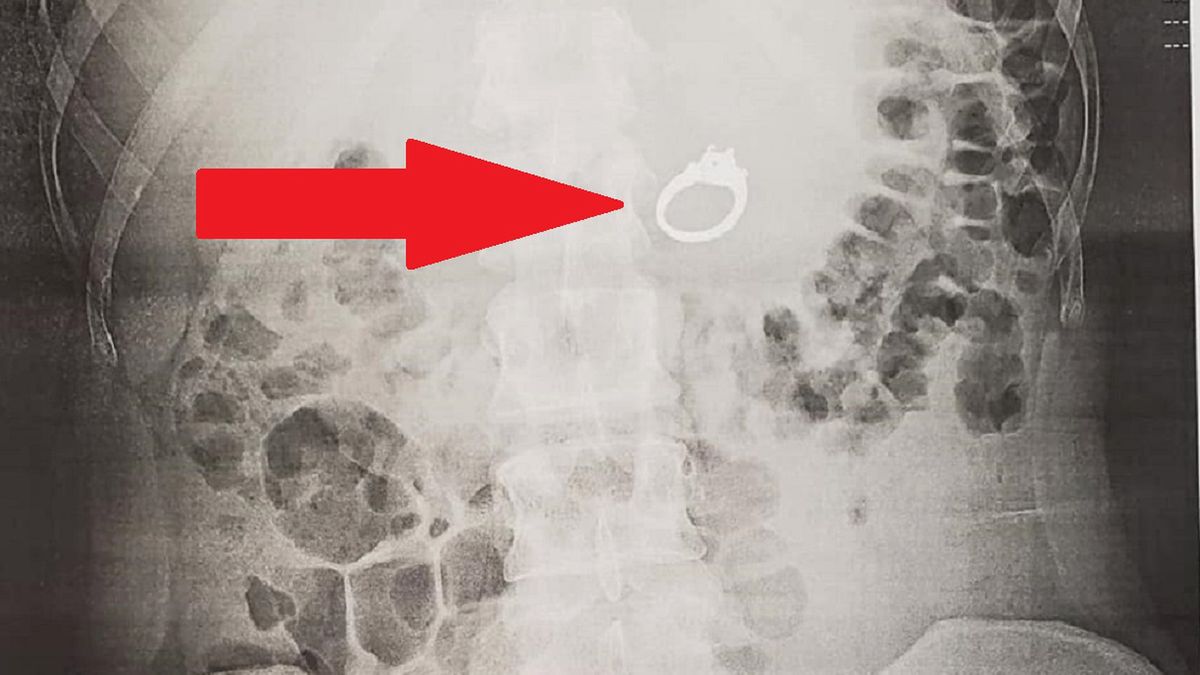

Przeżywała sen tak bardzo, że konieczna była interwencja lekarza. Narzeczona śniła o tym, że połknęła swój pierścionek zaręczynowy. Gdy się obudziła, okazało się, że zrobiła to naprawdę. Na szczęście Jenna Evans z San Diego w Kalifornii odzyskała cenny dla niej przedmiot.

Sen wpędził kobietę w kłopoty. Jennie Evans śniło się, że jechała pociągiem, gdy napadli na nią złodzieje. By uchronić swój pierścionek zaręczynowy, włożyła go do ust i połknęła. Gdy się obudziła okazało się, że pierścionek faktycznie zniknął z palca narzeczonej.

Amerykanka poszła do przychodni, gdzie została prześwietlona. Jenna Evans twierdzi, że kiedy lekarze wrócili z wynikami, byli zszokowani. W jej żołądku znajdował się pierścionek.

Kobieta została skierowana do gastroenterologa. Lekarz przeprowadził górną endoskopię i wyciągnął pierścionek z żołądka Jenny.